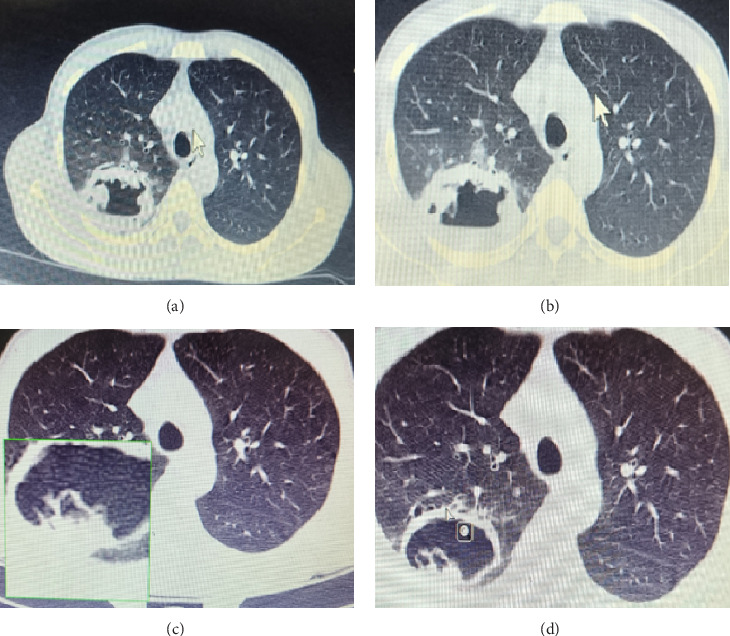

Opportunistic fungal infections (OFIs) are common among human immunodeficiency virus (HIV) -positive patients, especially in those with delayed diagnosis and treatment. Patients with severe HIV/AIDS with clusters of differentiation 4 (CD4) counts less than 100 are significantly prone to develop multiple OFIs. In the current study, we present a case of co-infection of pulmonary aspergillosis and cryptococcal meningitis in a late-diagnosed HIV patient with a low CD4 count.